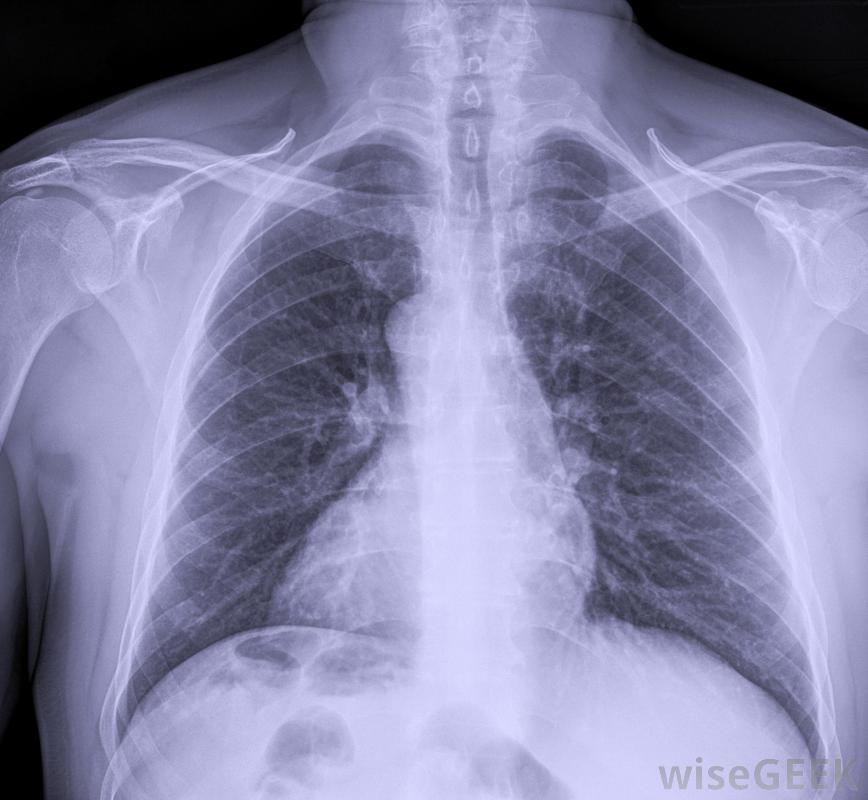

首字母縮略詞PICC代表外周插入中心導管。這是一種細長的導管,通常插入上臂的靜脈,然后將導管推進,直到尖端終止于靠近心臟的胸部靜脈。PICC線用于靜脈輸液和藥物的管理。在使用前,將進行胸部X光檢查,以確保PICC管路已正確放置。這些類型的靜脈輸液管可由受過專門培訓的護士、放射科醫生或醫生插入助手。這項手術通常在無菌條件下在床邊進行。超聲檢查上臂發現的大靜脈。在PICC線就位后,在使用該線之前,要進行胸部x光檢查以確認放置是否正確PICC線既可以用來給藥,也可以用來抽血。病人需要PICC的原因有很多一些病人可能需要長期化療或抗生素。這些外周插入的中心導管可以在原位放置數月,這使它們成為長期使用的理想選擇醫生和助手可能會插入PICC管路。過度肢體麻痹是患者需要PICC管路的另一個原因。這種靜脈輸液是為身體提供它需要通過靜脈補充維生素和營養素。高營養通常是給有腸道疾病而不能進食的人。在很多情況下,對高營養素的需求將持續數月。高營養素通常用于腸道疾病患者這種經外周插入的中心導管也可用于有出血障礙的病人。這些病人通常需要長期使用血液或血液制品。這些輸液可以很容易地通過PICC線進行。另一種這種類型的中心導管的優點是能夠從管道中抽取血液,這將避免患者多次被卡在血樣中。PICC管路用于靜脈輸液與任何類型的侵入性手術一樣,插入這種類型的導管也有風險。在插入過程中可能會發生空氣栓塞,這可能導致患者頭暈和呼吸短促。感染是一種風險,因為皮膚上有一個細菌進入的開口。插入時可能會造成神經損傷或刺激;這可能會導致手臂疼痛或四肢無力有些端口完全位于皮膚下,當導管尖端在心臟上方終止時,血栓或血凝塊形成的可能性很小,這種血凝塊可以在導管內或靜脈內形成本身。如果管道堵塞,護士可以在管道中注射一種特殊的藥物,幫助溶解血栓。一旦溶解,該線應易于沖洗。超聲波機用于顯示PICC線路上臂部的大靜脈一旦對PICC線的需求結束,就可以很容易地將其拆除。這可以由護士或其他經過適當培訓的醫護人員來完成。一旦拆除了PICC線,就要測量其長度,以便與插入長度進行比較。這將確認所有的線路都被拆除了在某些患者中,由于血液凝塊或手臂靜脈的問題,PICC線可能被放置在胸部。